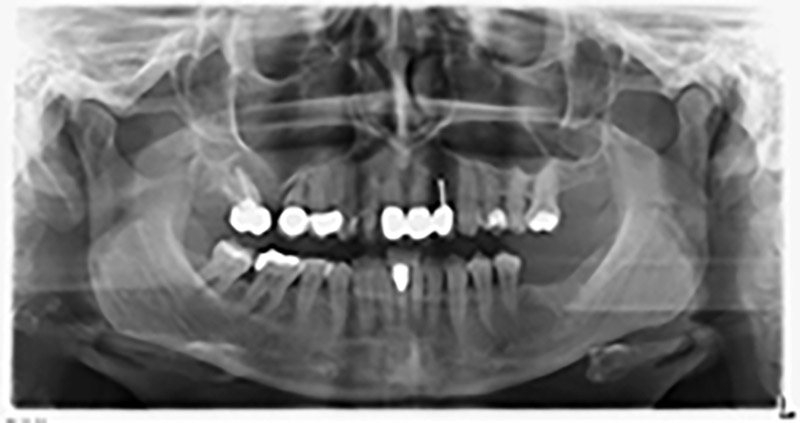

About six months after teeth 16 and 14 were extracted, a digital volume tomography (DVT, Planmeca) examination was performed for planning and risk minimization purposes. It clearly showed that the bone had not regenerated to the desired volume (Fig. 2 to 7).

To restrict the augmentation to region 14, and in consultation with the patient, it was planned that implant 16 would be placed, inclined, in the dorso-cranial direction (Fig. 8).